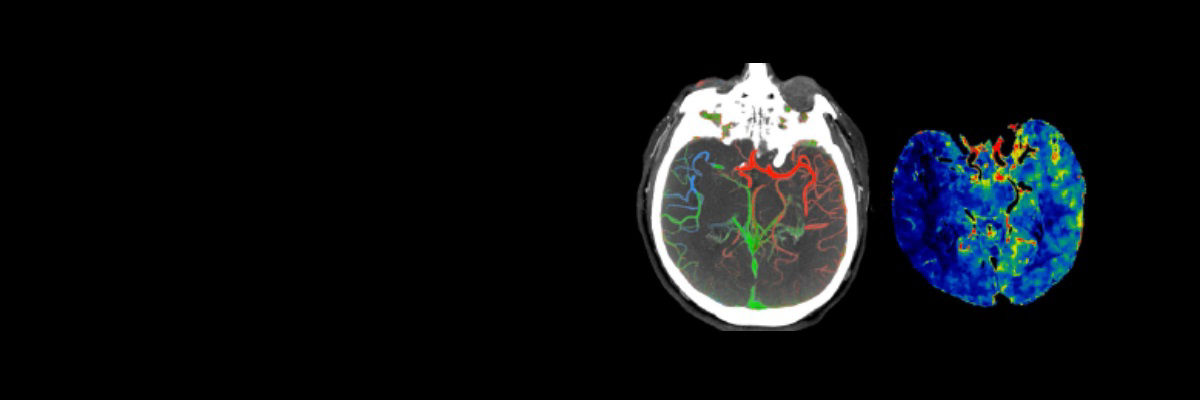

A patient with suspected TIA or stroke receives a general and neurological examination followed by diagnostic brain imaging, performed immediately on arrival so that treatment can be started promptly. 3 Optimal scanning coupled with workflow applications and protocols designed for stroke help deliver accurate and quick diagnosis to impact patient outcomes.

<p>FastStroke CT Application</p>

Read More

<p>Fast Brain protocol with HyperWorks</p>

Acute ischemic stroke is a complex disease and successful endovascular treatment is based on the comprehensive ability to rapidly integrate multiple pieces of information.4 Initiate Intravenous thrombolysis (IV-tPA) if less than 5 hours of ischemic stroke. Initiate mechanical thrombectomy within 6 hours of onset of large vessel stroke (MCA territory). Fast interventions with accurate imaging can help reach lesions quickly to help improve patient outcomes.